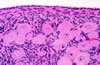

Hücreden ve damardan zengin jelatinimsi bir yapı (supendimal germinal matriks)dır.